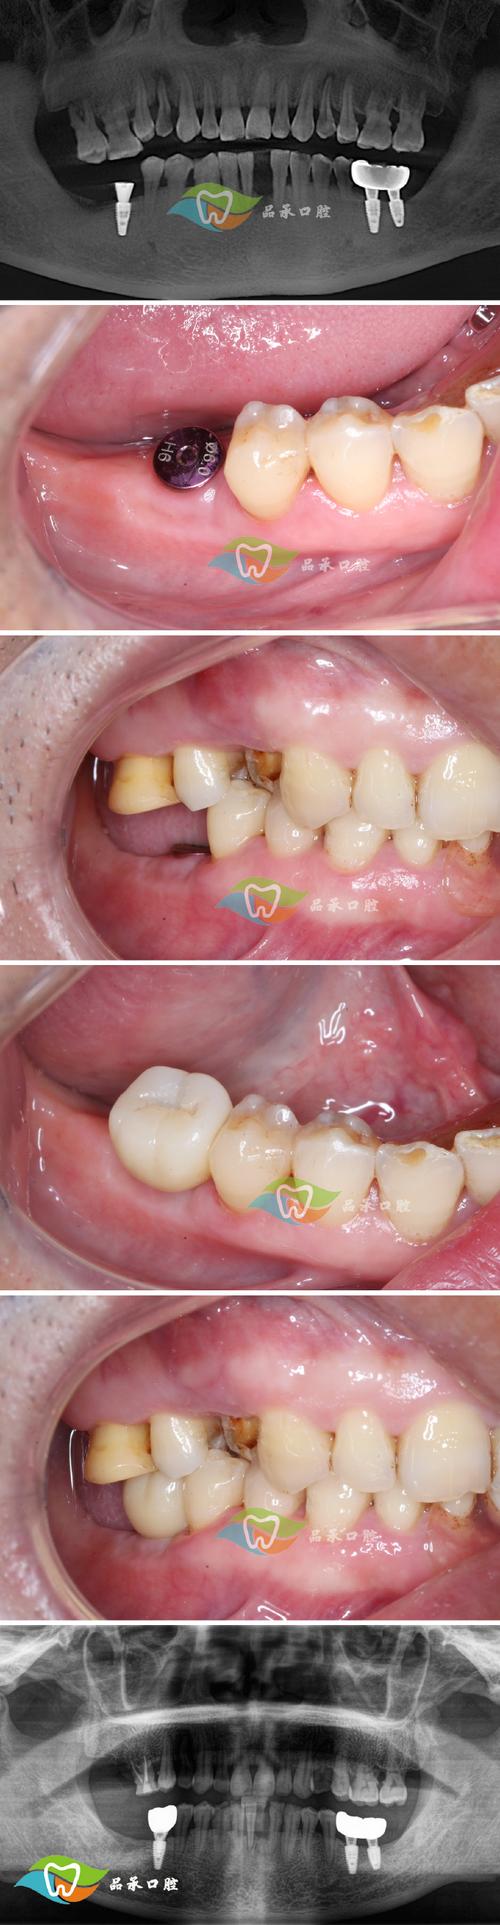

一是手术相关的技术问题,种植体的成功依赖于与牙槽骨的骨结合(osseointegration),即种植体表面与骨组织形成直接的 structural connection,若术中种植体植入位置不佳,如靠近下颌神经管、上颌窦等重要解剖结构,为避免损伤,医生可能被迫选择骨质较薄或血供较差的区域,会影响骨结合效果;或种植体植入角度偏差过大,导致受力不均,长期咀嚼后可能出现松动,手术中若产热过多(如钻速过快、未充分冷却),可能损伤周围骨细胞,导致骨吸收,进而引发种植体松动。

二是术后愈合阶段的因素,骨结合通常需要3-6个月,此期间若患者过早使用种植体咀嚼硬物,或受到外力撞击,可能导致种植体与骨界面微动,干扰骨愈合,部分患者存在吸烟、糖尿病等基础疾病,会影响局部血液循环和骨代谢,延缓骨结合速度,甚至导致结合失败,术后口腔卫生维护不当,如种植体周围堆积牙菌斑和牙结石,可能引发种植体周围炎,炎症会破坏牙槽骨,导致种植体“失去支撑”而晃动。

| 骨结合失败 | 种植体明显松动,无疼痛(早期)或伴疼痛(晚期),X线显示种植体周围透射影 | 根据松动程度,可能需取出种植体,待骨愈合后重新植入 |

长期治疗阶段,需根据根本原因采取不同措施,对于种植体周围炎,除基础清洁外,可能需进行翻瓣手术,彻底清除种植体表面的菌斑和牙结石,必要时植骨以修复骨缺损;若骨结合失败且松动严重,种植体已无法保留,需手术取出,待3-6个月牙槽骨愈合后评估是否二次植牙,对于咬合习惯不良(如夜磨牙)患者,需佩戴咬合垫,保护种植体避免异常受力;若因骨吸收导致松动,且松动程度较轻,可通过植骨术增强骨支持,必要时更换更长的种植体以增加稳定性。

需要强调的是,植牙后牙根晃动的预后与发现和处理时机密切相关,早期发现(如轻微松动、无骨吸收)且及时干预,多数种植体可保留;若拖延至严重骨吸收或种植体明显移位,则可能面临种植体失败的风险,定期复查至关重要——植牙后第1年建议每3个月复查1次,之后每年至少复查1次,医生可通过专业检查及时发现潜在问题,避免小问题演变成大麻烦。

为降低植牙后牙根晃动的风险,术前、术中及术后均需做好充分准备和护理。术前评估是关键,医生需通过CBCT、全景片等检查评估牙槽骨的厚度、高度及密度,排除炎症、囊肿等病变;患者需如实告知医生自身健康状况(如糖尿病、骨质疏松、吸烟史),医生会判断是否适合植牙或需先控制基础疾病。术中操作需规范,选择经验丰富的医生,严格遵循无菌原则,控制钻速和冷却,确保种植体植入位置、角度合适,为骨结合创造良好条件。术后护理需到位,术后1周内避免用患侧咀嚼,避免食用过硬、过黏食物,保持口腔卫生(刷牙、使用牙线、冲牙器),戒烟限酒,遵医嘱服用抗生素和止痛药;骨结合期内避免剧烈运动和外力撞击,定期复查,确保种植体周围健康。